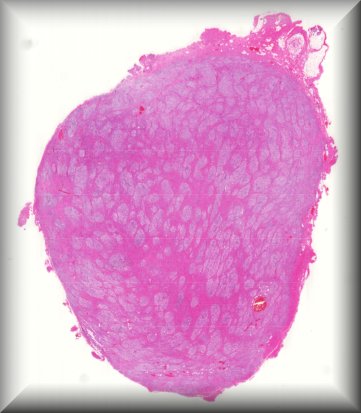

Paul van der Valk (Amsterdam): Orbital tumour. |